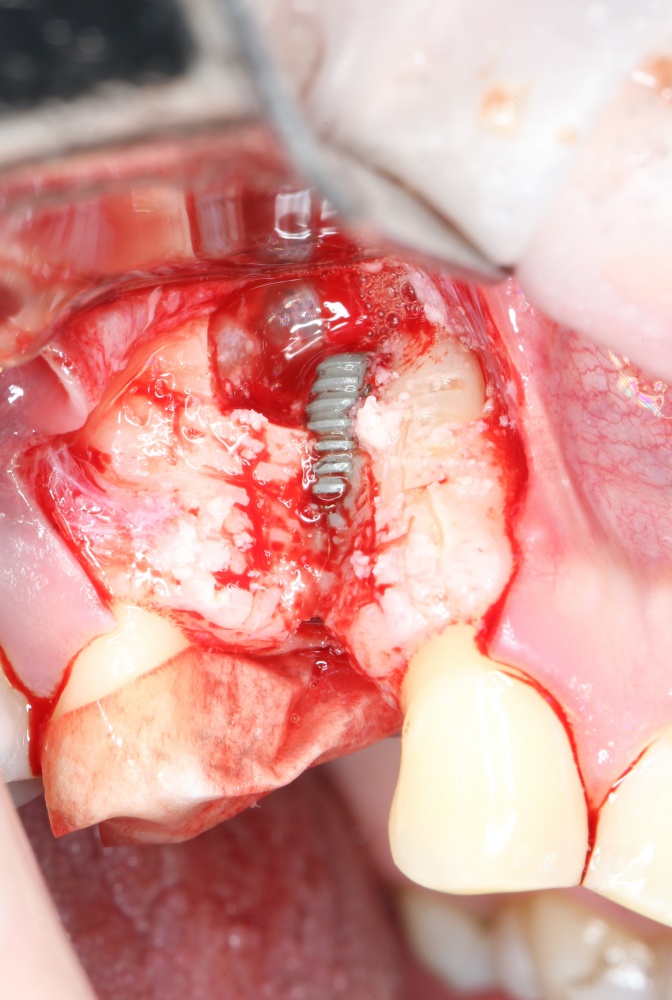

Далее, можем приступить к установке имплантатов. Разумеется. по хирургическому шаблону:

Последняя картинка даёт представление о том, какой объем костной ткани мы «нарастили».

Поскольку принимающее ложе и аутокостный блок конгруэнтны, мы можем отказаться от использования барьерной мембраны. Она не нужна.